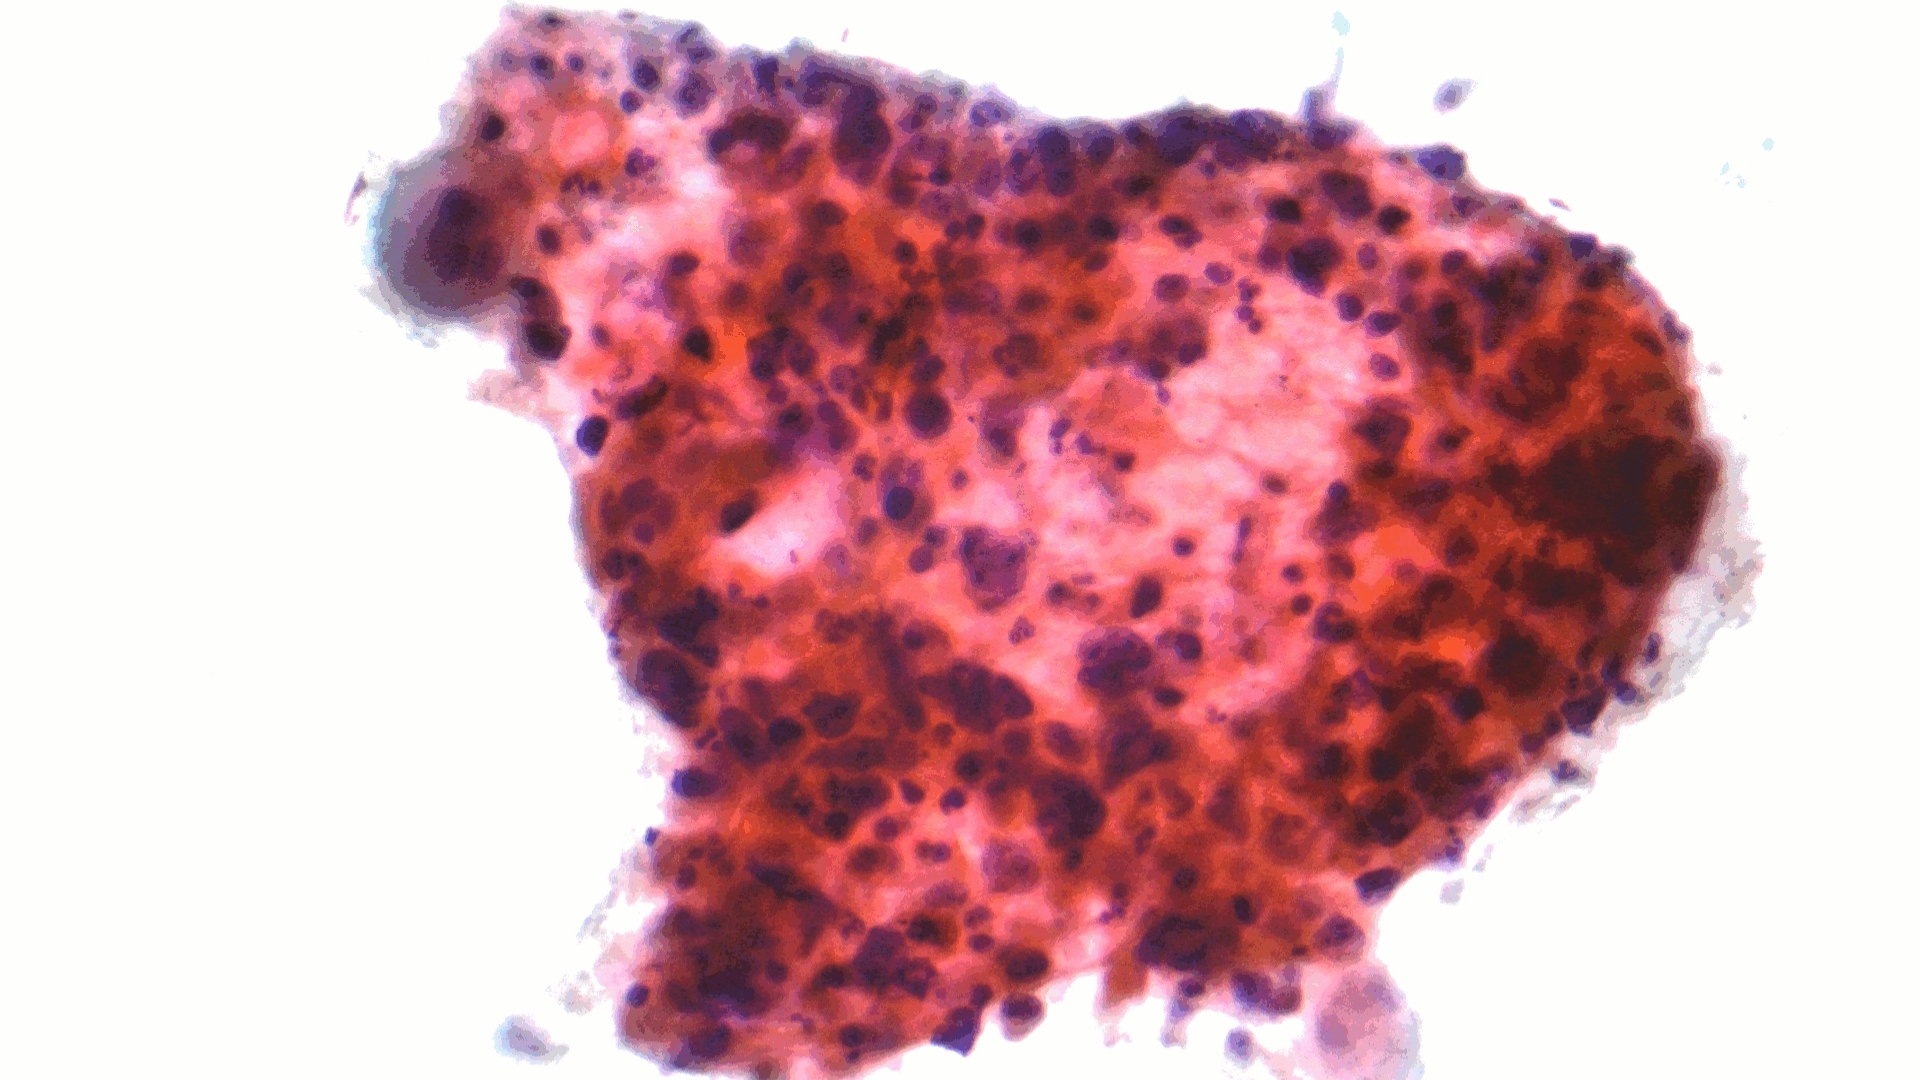

Non-Small Cell Lung Cancer (NSCLC) represents approximately 85% of all lung cancers, profoundly impacting millions globally each year. Understanding Non-Small Cell Lung Cancer (NSCLC) begins with recognizing it as a diverse group of cancers originating from lung epithelial cells. This classification includes adenocarcinoma, squamous cell carcinoma, and large cell carcinoma, each with distinct biological features and behaviors.

Types of Non-Small Cell Lung Cancer (NSCLC)

• Adenocarcinoma – Most common type, often appearing in the outer regions of the lungs and associated strongly with non-smokers or former smokers.

• Squamous Cell Carcinoma – Typically found centrally within major bronchi, closely connected to long-term smoking.

• Large Cell Carcinoma – Least common form, rapidly spreading and captures metabolic-dependent aggressiveness.